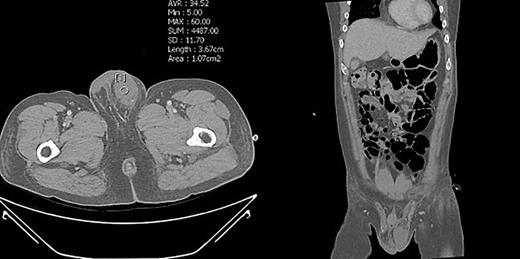

To prevent the patient from further self-injury, simple therapeutic restraint of both arms was performed with the patient’s consent, and sedative medication was administered. He was closely observed in the intensive care unit to monitor his hemoglobin and systemic conditions. Additional transfusion treatment was provided as needed. Psychiatric medicines including antipsychotics and sedatives (Clozapine 125–250 mg/day, haloperidol 2.5–5 mg, and lorazepam 1–2 mg/day) were prescribed by a psychiatrist. After 5 days of taking the psychiatric medication, the patient no longer reported the impulse to harm himself, and was able to release the simple restraint on both arms. No further self-harm occurred until he was discharged, presumably due to the proper effects of taking psychiatric medication. Anticoagulant agents (5 mg apixaban, twice per day), subcutaneous heparin injection (5,000 IU, twice per day), and alprostadil (10 mg, once per day) were given for circulation to prevent the thrombosis of vessels. On POD2 from the first operation, a testicular scan with technetium pertechnetate revealed the viability of the remnant left testis compared with the amputated right testis (Fig. 7). On POD4, contrast-enhanced CT showed the enhancement of the vessel into the testis (Fig. 8). On POD7, scrotum Doppler ultrasonography revealed the Doppler signal in the parenchyma of the testis (Fig. 9). Testosterone levels increased after the surgeries and normalized on POD5 (Fig. 10). He was discharged on POD9 without any skin complication (Fig. 6c). After discharge, he returned to our clinic for follow-up on POD13 and 23. On the visit, laboratory follow-up including testosterone and free testosterone was checked and confirmed as normal (Fig. 10).

We performed five examinations to check the viability of the replanted testis. First, in the operating room, we used indocyanine green after replantation (Fig. 4). Indocyanine green fluorescence perfusion showed testicular perfusion, which enabled the immediate checking of the viability of vessels. This procedure is appropriate for checking the viability of microscopic vessels that may be damaged during a milking test. Second, a testicular scan showed the viability of the testis (Fig. 7). One testis is markedly different from the lesion of orchiectomy. However, the scan resolution was low because of a wide range of arterial courses and the disturbance of the urethral catheter or bladder. Third, contrast-enhanced CT displayed the vascularity of the testis and the surrounding parts (Fig. 8). However, the shooting time to the enhanced phase could affect the failure of the vascularity of the testis. No protocol for this case has been established in our institute; therefore, CT was a nonspecific tool for testicular examination. Fourth, ultrasonography efficiently showed the vascularity inside the testis (Fig. 9). However, skin wound could inhibit or limit ultrasonography. Fifth, we indirectly checked the testicular function based on testosterone levels (Fig. 10). A laboratory examination should be performed continuously. However, this procedure could be limited among hypogonadal men, and the separate testicular function of each testis could not be easily identified. Nevertheless, these techniques will help determine the viability of the testis in specific situations.